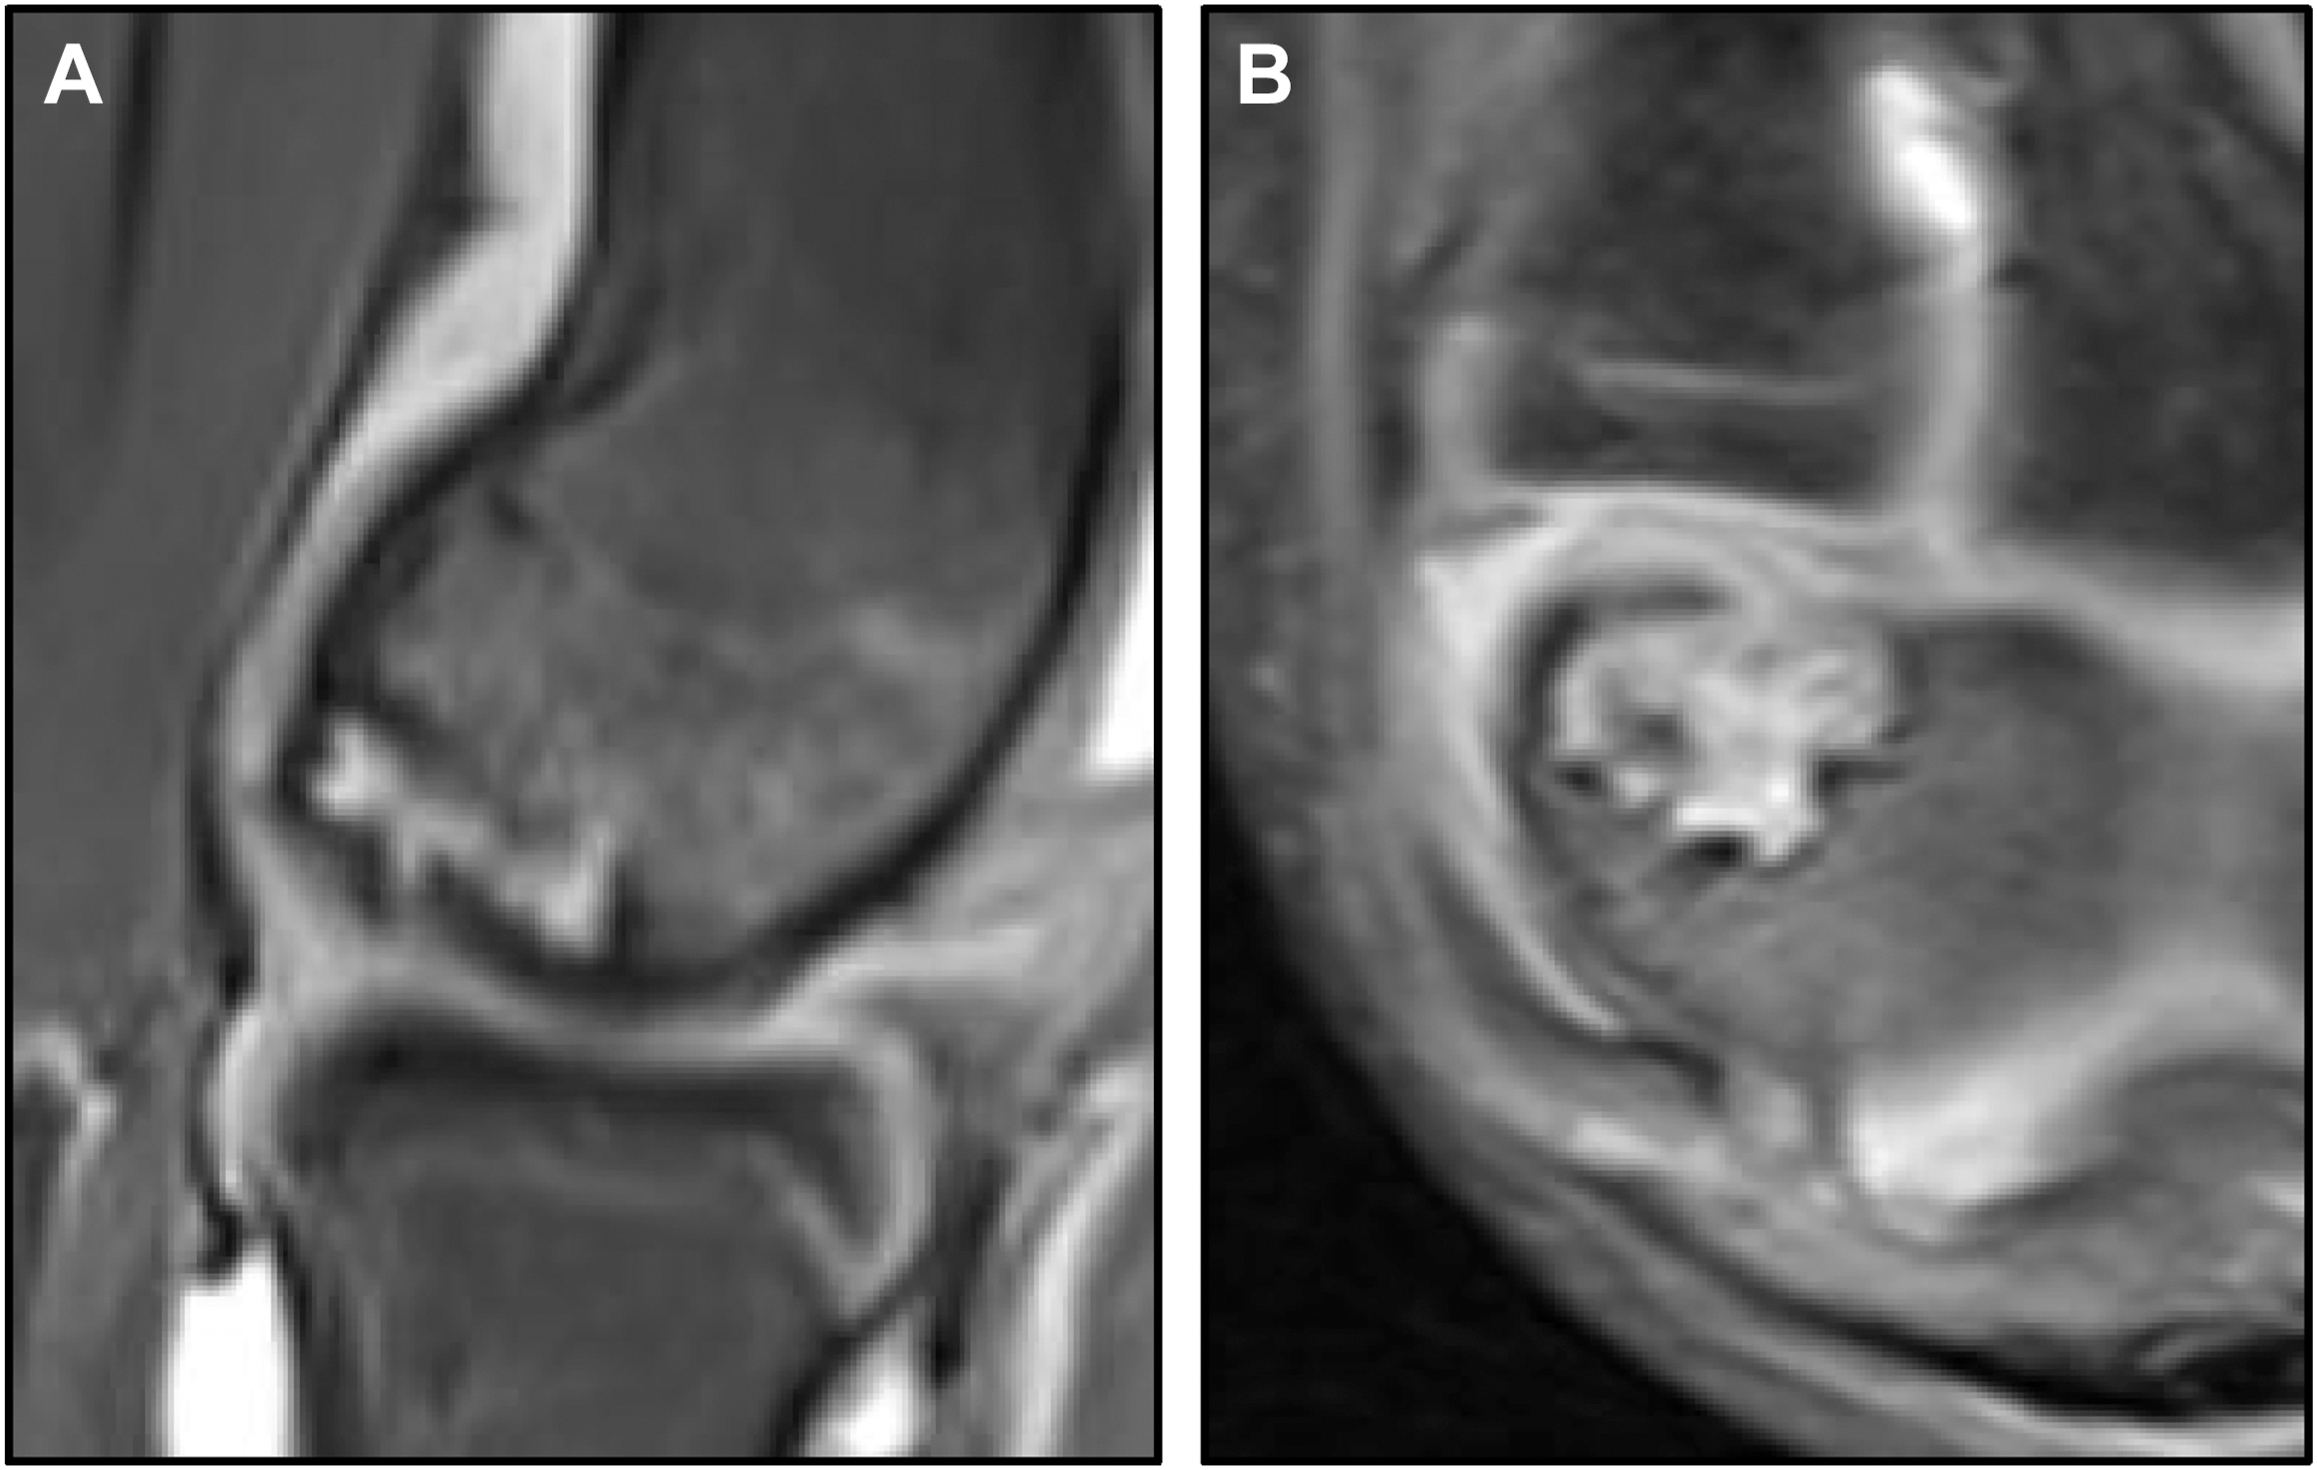

Standard orthogonal radiographs have been reported to miss up to half of all OCD lesions and are less than 50% sensitive when compared to MRI. , Thus, routine radiographs are not typically useful for treatment planning or follow-up imaging. First described by Takahara and colleagues and Conway, the 45° flexed AP “capitellum view” is widely accepted as the standard of care for initial imaging workup in these patients as it is better able to visualize the capitellum. In baseball players, it is our recommendation that flexed views are obtained at 40° and 60° in throwers as they have been found have larger lesions with higher inclination angles. Advanced imaging modalities such as computed tomography (CT) and MRI have been shown to be more valuable in not only identifying lesions but also evaluating and characterizing their stability. MRI scans are almost always performed with intra-articular contrast with a high spatial resolution magnet, narrow slices (2–3 mm) with 3 dimensional reformats. It is our recommendation that MRI scans are performed with “40° up-oblique” sequences, allowing slices to be appropriately aligned with the OCD lesion ( Fig. 3 ). CT scans are typically only useful for complex, late-stage reconstruction planning, and recent studies have begun to suggest that ultrasonography may even provide an improved screening tool capable of detecting asymptomatic lesions. ,

The treatment of OCD is still largely evolving but is mainly predicated on the stability of the overlying cartilage, the size and location of the lesion, and the lesions capacity to heal (often related to age). Many classification systems exist for a multitude of imaging modalities seeking to grade these lesion characteristics to guide treatment; however, they are typically unreliable and difficult to apply. Overall, general signs of instability on imaging include fluid beneath the lesion, increased T2 signal at the fragment/bed interface, sclerosis, and fragmentation of the cartilage or subchondral plate with associated loose bodies ( Fig. 4 ). , ,